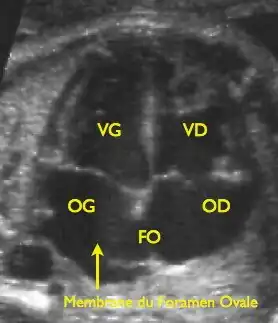

VG: linker ventricel, VD: rechter ventrikel, OG: linkeratrium, OD: rechteratrium, FO: foramen ovale | ||||